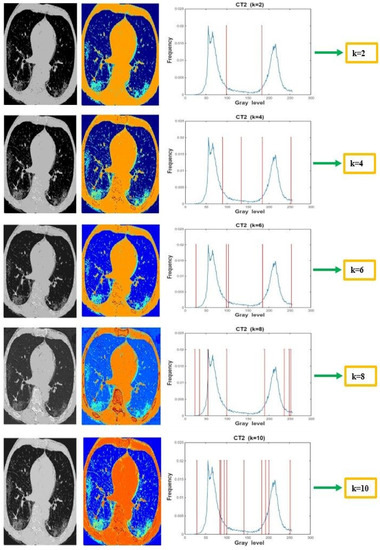

Levy Flight and Chaos Theory-Based Gravitational Search Algorithm for Image Segmentation

by Sajad Ahmad Rather and Sujit Das

Mathematics 2023, 11(18), 3913; https://doi.org/10.3390/math11183913 - 14 Sep 2023

Cited by 7 | Viewed by 2257

Abstract

Image segmentation is one of the pivotal steps in image processing due to its enormous application potential in medical image analysis, data mining, and pattern recognition. In fact, image segmentation is the process of splitting an image into multiple parts in order to [...] Read more.

Image segmentation is one of the pivotal steps in image processing due to its enormous application potential in medical image analysis, data mining, and pattern recognition. In fact, image segmentation is the process of splitting an image into multiple parts in order to provide detailed information on different aspects of the image. Traditional image segmentation techniques suffer from local minima and premature convergence issues when exploring complex search spaces. Additionally, these techniques also take considerable runtime to find the optimal pixels as the threshold levels are increased. Therefore, in order to overcome the computational overhead and convergence problems of the multilevel thresholding process, a robust optimizer, namely the Levy flight and Chaos theory-based Gravitational Search Algorithm (LCGSA), is employed to perform the segmentation of the COVID-19 chest CT scan images. In LCGSA, exploration is carried out by Levy flight, while chaotic maps guarantee the exploitation of the search space. Meanwhile, Kapur’s entropy method is utilized for segmenting the image into various regions based on the pixel intensity values. To investigate the segmentation performance of ten chaotic versions of LCGSA, firstly, several benchmark images from the USC-SIPI database are considered for the numerical analysis. Secondly, the applicability of LCGSA for solving real-world image processing problems is examined by using various COVID-19 chest CT scan imaging datasets from the Kaggle database. Further, an ablation study is carried out on different chest CT scan images by considering ground truth images. Moreover, various qualitative and quantitative metrics are used for the performance evaluation. The overall analysis of the experimental results indicated the efficient performance of LCGSA over other peer algorithms in terms of taking less computational time and providing optimal values for image quality metrics. Full article

(This article belongs to the Section E1: Mathematics and Computer Science)

Show Figures

Graphical abstract